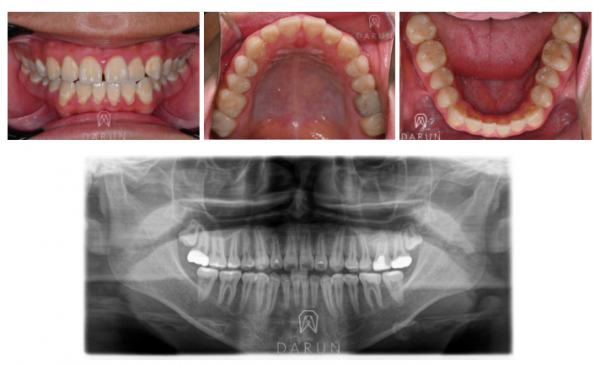

치아 희끗히끗 한것들이 많아요.

뭔가 노르스름한것들도 같이 보이구요.

이런 것들은 후천적 요인 이라기보단,

선천적으로 치아 저 광화 되있을 가능성이 많아요.

이런 치아들을 가지고 계신 분들이라면

관리를 굉장히 잘하셔야 됩니다.

일반적인 상황보다 치아 강도가 많이 떨어집니다.

왼쪽 위 큰 어금니쪽에 뭔가 거무스름한게 보입니다.

아주 무서워보이는 색이에요.

레진으로 굉장히 광범위하게

파괴된 곳에 치료를 받으셨고,

충치가 심해서 신경치료도 받은 걸로 보여요.

이 경우에 크라운은 필수적입니다.

환자분 선천적인 치질 자체가 약하다는 것도 있지만,

소실된 치아량 이 너무 광범위해서

어떻게든 치아를 기계적으로 강화시켜줘야해요.